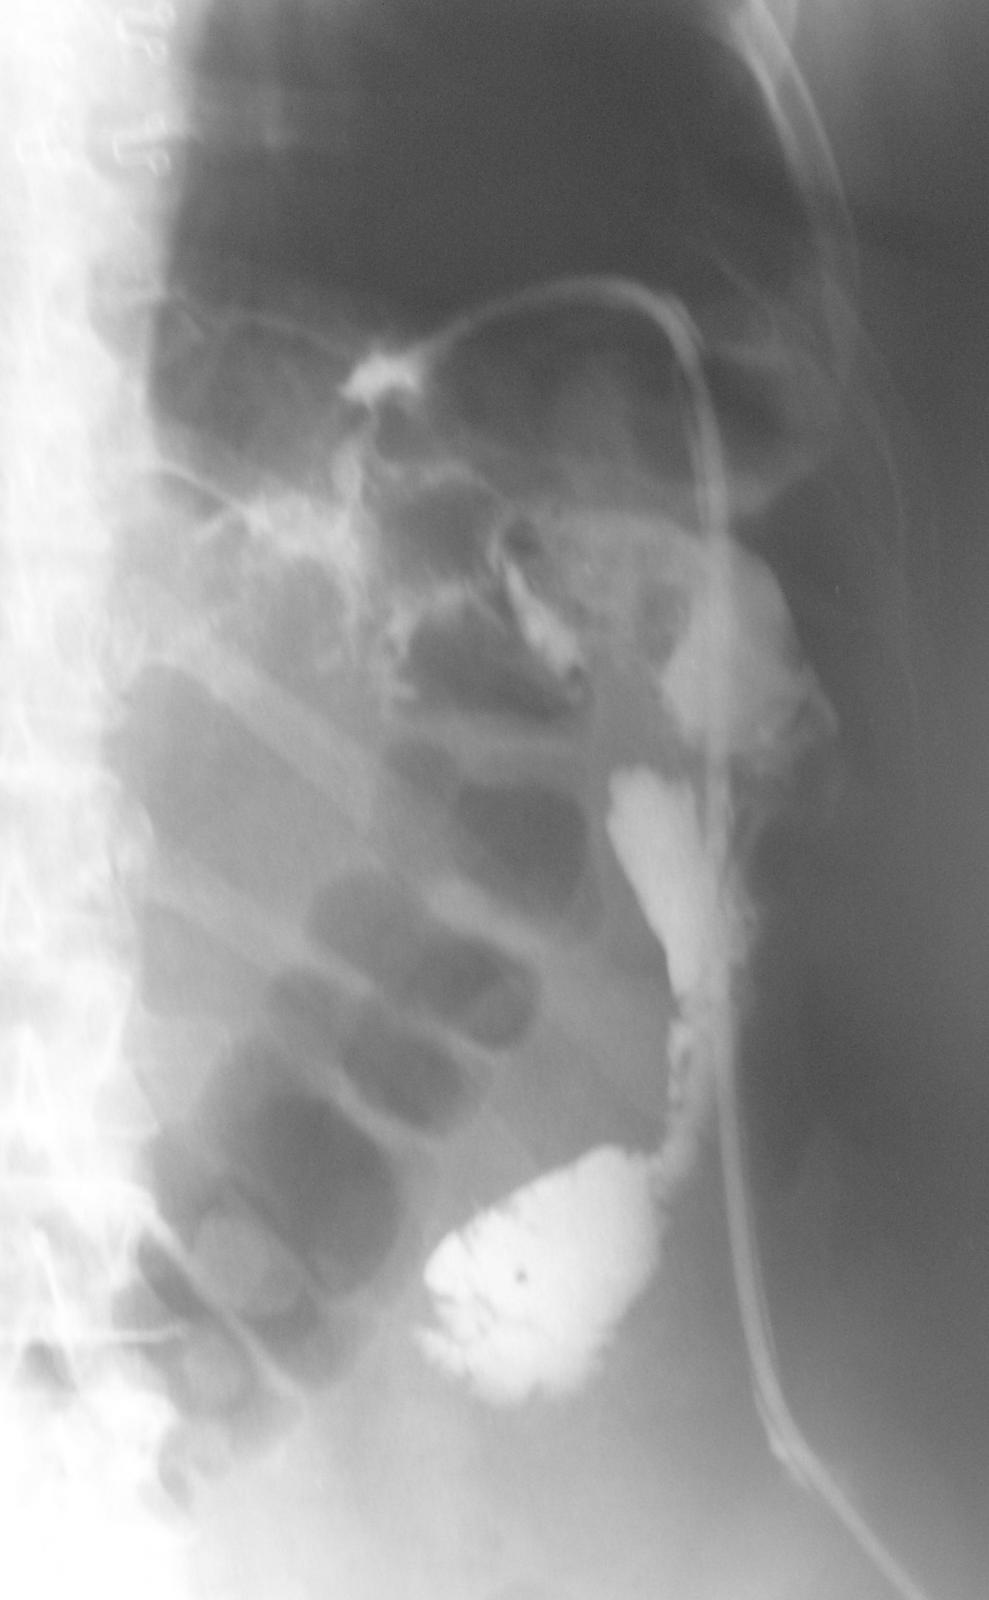

Фистулография.

Фистулография — это вид рентгенологического исследования свищевых ходов (или фистул) с применением контрастного вещества.

Метод фистулографии очень эффективен для определения направления, протяженности, разветвлений свищевого хода, выявления образовавшихся по его ходу полостей и взаимоотношений с соседними органами.

Перед фистулографией посредством шприца удаляют содержимое свищевого канала, промывают его. Во время фистулографии во внешнее свищевое отверстие вставляют иглу или катетер и вводят рентгеноконтрастное вещество- чаще всего это омнипак.

Объем вводимого вещества зависит от размера и глубины свища (главное правило: пространство должно быть заполнено доверху). Затем заполненное отверстие плотно прикрывают шариком из марли, заклеивают медицинским клеем или лейкопластырем и готовят несколько рентгенологических снимков в различных проекциях. После проведения фистулографии контрастное вещество удаляют, или оно вытекает самостоятельно. Иногда фистулографию делают под анестезией.